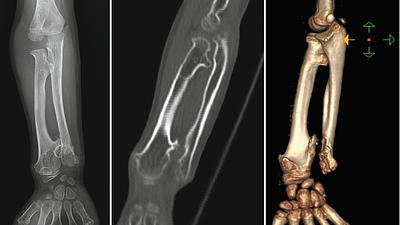

pesquisadores.jpg

Pesquisadores criam prótese contra infecções

11/07/2025, 12:41

Um projeto desenvolvido por pesquisadores paranaenses pretende ajudar a mudar esse percurso, com uma prótese biodegradável, fabricada em impressora 3D.